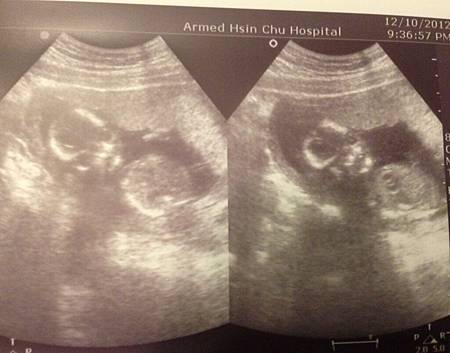

照片中的真的長得很像腳丫丫

可他千真萬確的是手兒

咦?怎麼只有四個手指頭?

醫生:免擔心,他的大拇哥在後面

(小籠包OS:媽,樂透記得買四號啊!)

小籠包的週數都很標準的照著時間走,沒有過大也沒有過小

這一週還是跟上週一樣大部份肉肉都還沒長得太多

所以看起來超驚悚的啊

都是骨頭的骷顱頭